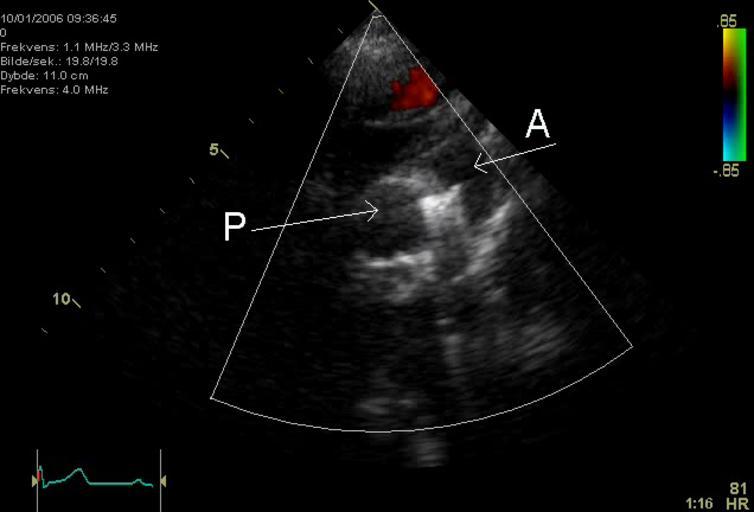

MAKE A MEME View Large Image PDA Coil.png An echocardiogram of a coiled persisting ductus arteriosus One can see the aortic arch the pulmonary artery and the coil between them Image made by myself Kjetil Lenes Released in agreement with my employer Keywords en ...

Keywords: PDA Coil.png An echocardiogram of a coiled persisting ductus arteriosus One can see the aortic arch the pulmonary artery and the coil between them Image made by myself Kjetil Lenes Released in agreement with my employer Keywords en Echocardiography Sonography Ultrasonography Medical Ultrasound Cardiology persisting ductus arteriosus de Echokardiographie Sonografie Sonographie Ultraschall Kardiologie ductus arteriosus Echocardiography Patent ductus arteriosus